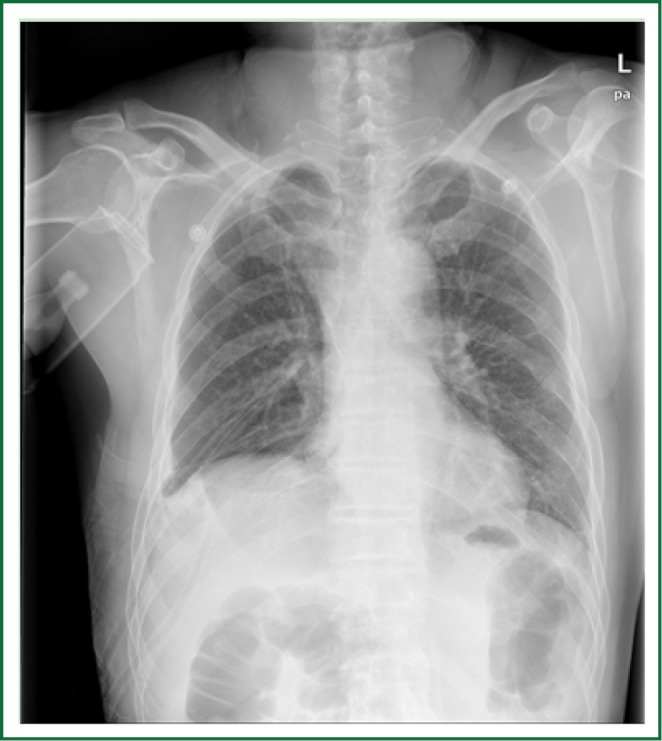

About 200 mL slightly bloody discharge was drained via the tubes 24 hours after the surgery, and no obvious pulmonary air leak was found. Chest X-ray performed 24 hours after the surgery showed that the recruitment of the residual lungs was good, and no obvious effusion or air leak was found in the right thoracic cavity (Figure 3).

Figure 3.

Chest X-ray performed 24 hours after the surgery.